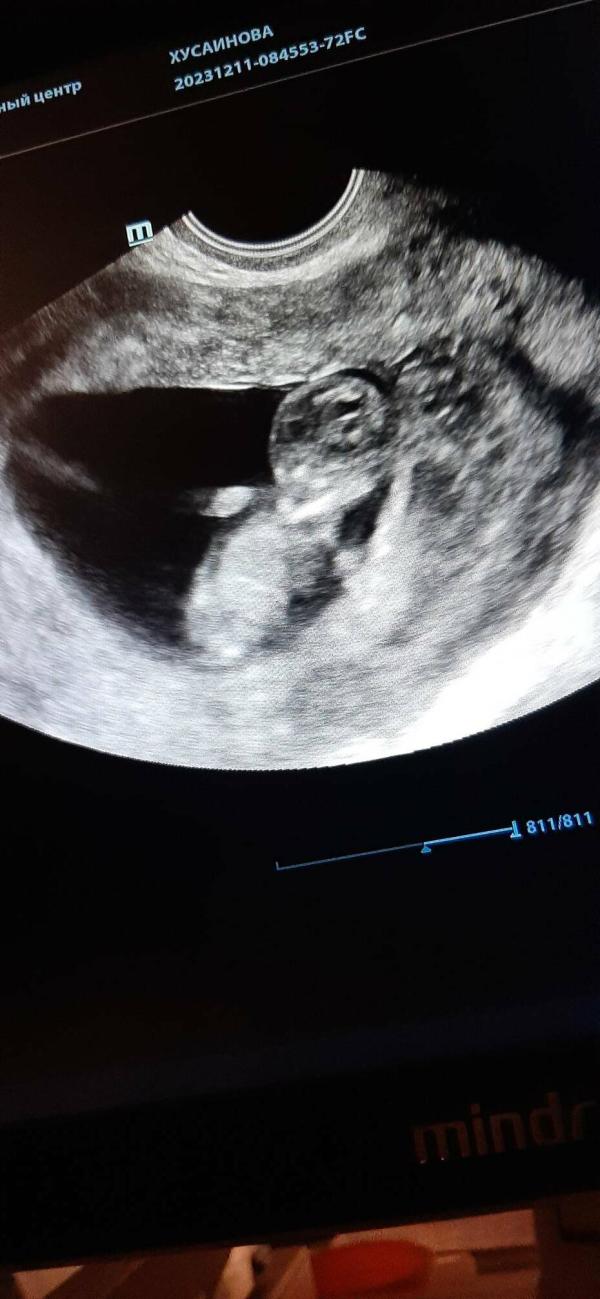

Сходила на узи,срок отличается но я и подозревала позднюю овуляцию.показали моего головастика❤все хорошо,но назначили повторное узи через неделю. Мне стало спокойнее как сказали что живой и сердечко бьётся )))